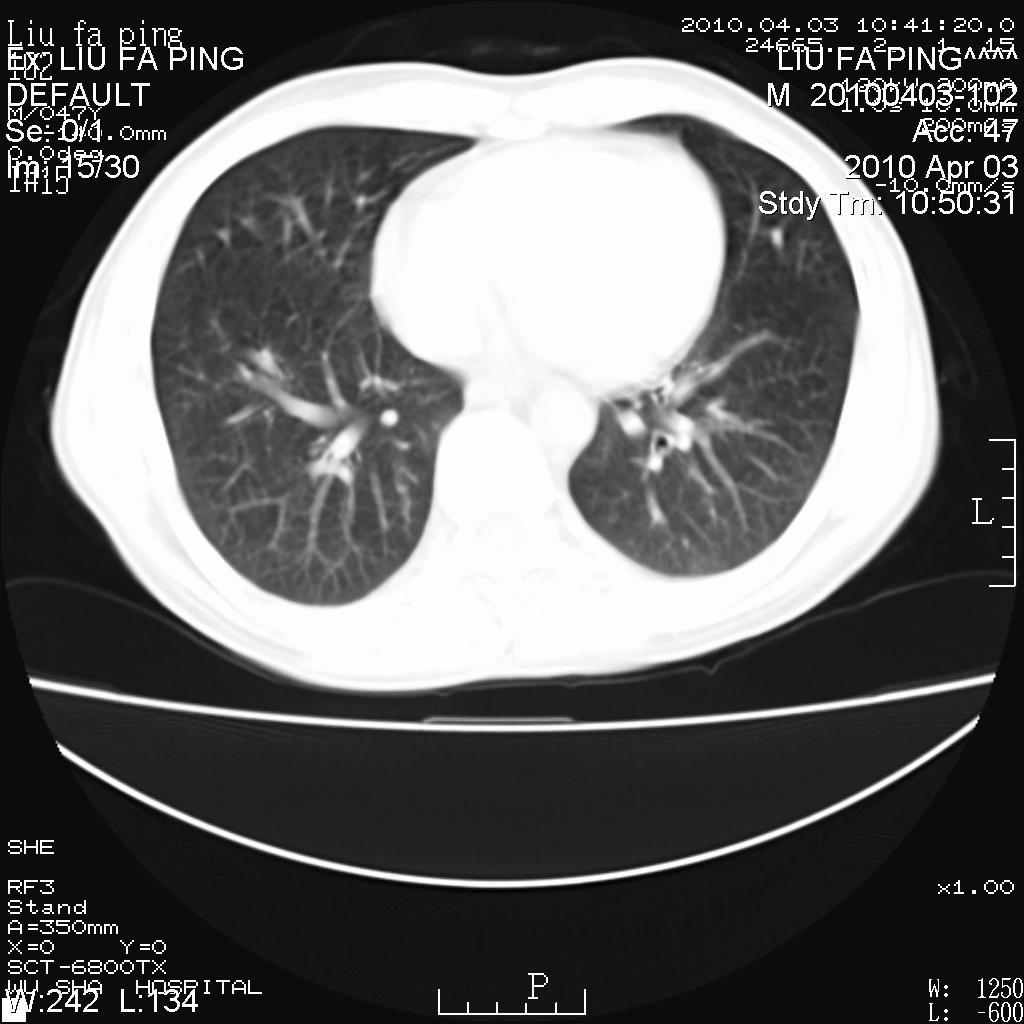

标题: CT25875:咳嗽数天。

平时身体健康,无不适

男性47岁,考虑中心性肺癌合并阻塞性肺炎,纵膈淋巴结肿大。肺内及纵膈淋巴结钙化。

建议支气管镜检

支持右侧中央型肺癌伴右肺上叶阻塞性炎症、纵膈淋巴结转移,建议纤支镜检查!

男性47岁,考虑中心性肺癌合并阻塞性肺炎,纵隔淋巴结肿大。肺内及纵隔淋巴结钙化。

考虑右肺中央型肺癌并阻塞性肺炎,右肺门及纵隔淋巴结转移;建议必要时行纤支镜检查进一步明确诊断。